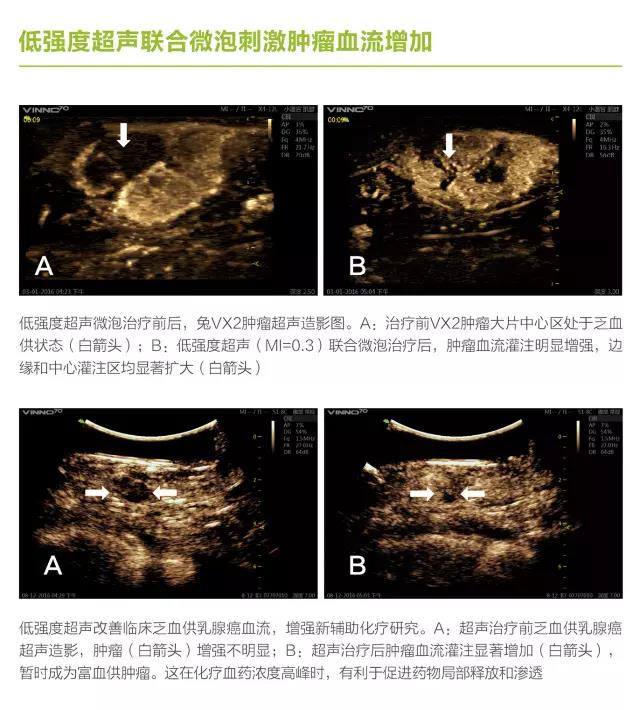

第三軍醫(yī)大學(xué)第二附屬醫(yī)院劉政教授長(zhǎng)期從事超聲空化研究,與飛依諾公司合作推出了在診斷超聲劑量下利用超聲空化效應(yīng)完成診斷與治療新機(jī)型 VINNO70超聲診療一體機(jī)。

VINNO70 超聲診療一體機(jī)在常規(guī)超聲診斷的基礎(chǔ)上,增加了V Flash超聲空化功能,多參數(shù)可調(diào)滿足了微氣泡諧振、膨脹、內(nèi)爆等的控制